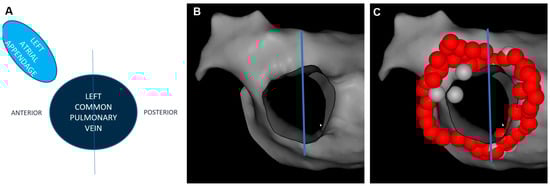

2.3. Ablation Index and Interlesion Distance Guided PVI

2.4. Postprocedural Assessment of Interlesion Distance

| LCPV, n | 18 (14%) | 21 (16%) | 0.4 |